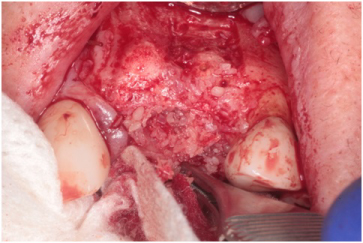

Using bilateral papillae sparing releasing incisions at surgical sites, the Cytoplast® membranes and tacks were removed and the implant sites were prepared showing excellent bone regeneration (Figures 20, Figure 21, and Figure 22). Standard protocol was used to prepare Straumann® Bone Level Tapered implants (Andover, MA, USA). (Figures 20 and Figure 22). Four months post implant placements with all 3 implants osseointegrated and provisional restorations in place. (Figures 23, Figure 24, and Figure 25).

Figure 20: Implant site preparation for a 3.3 × 10 mm Straumann Bone Level Tapered implant. Depth gauge is in place. Notice the amount bone regeneration. View Figure 20

Figure 21: 4-months post-op guided bone regeneration at the #s 9 and 10 sites. Notice the bone regeneration compared to the pre-op condition. View Figure 21

Figure 22: Straumann Bone Level Tapered implants placed at the #s 9 and 10 sites. View Figure 22